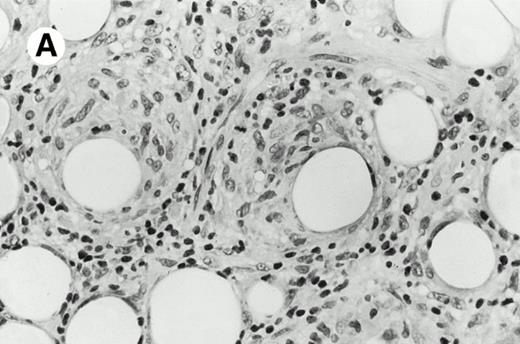

All cases were studied for cytotoxic markers. All of them demonstrated a strong granular cytoplasmic positivity for the cytotoxic granule-associated protein TIA-1. A variable proportion of neoplastic cells were also found positive with Granzyme B (Fig 4A and B) in all cases. Staining for perforin was performed on frozen sections in nine cases, of which seven were positive, one was negative, and the remaining was not interpretable.

Granzyme B expression. (A) Strong paranuclear staining of neoplastic cells in a nasal lymphoma (case no. 3); (B) strong cytoplasmic staining of a few neoplastic cells surrounding intestinal glands in an enteropathy-associated γδ T-cell lymphoma (case no. 11). (Paraffin-embedded section, APAAP technique.)